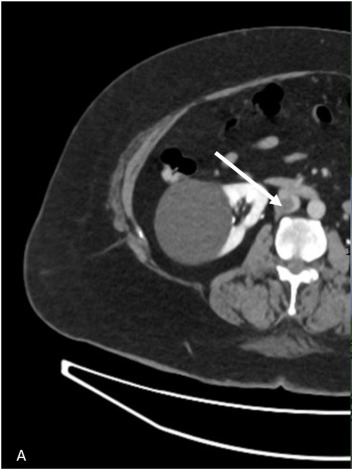

A. CT显示IVC(白色箭头)中血栓的近端范围, |

B. 右下肢浅表水肿(虚线箭头) |